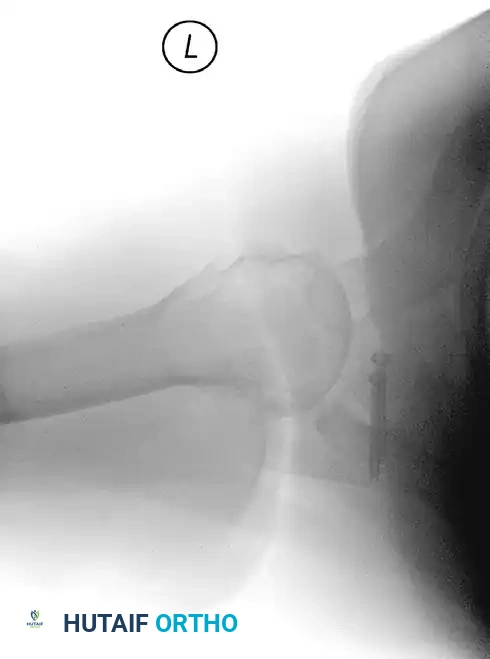

Postoperative West Point axillary radiograph showing restoration of the anterior glenoid surface and flush graft positioning.

Image